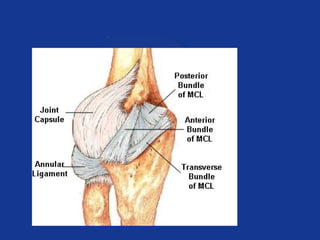

Medial Collateral Ligament (MCL)

Anterior

Medial

Collateral

Ligament

Posterior

Resists valgus

forces

Limits extension

Transverse ligament